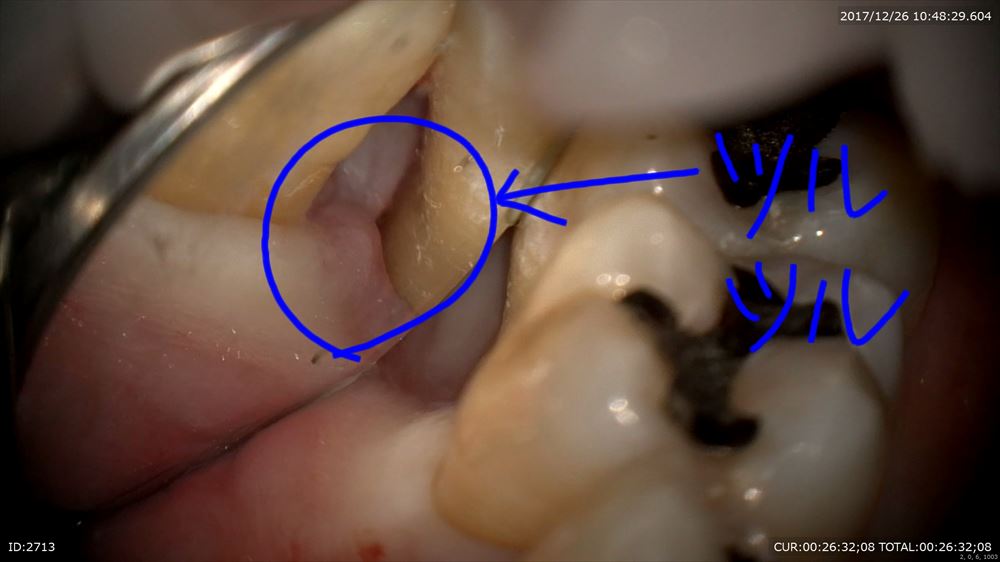

最後は精密根管治療のケース。根管が細くレントゲンでも石灰化が認められました。困った。マイクロスコープで探していきます。

ここまで拡大できました。4つ根っこがあったのです。